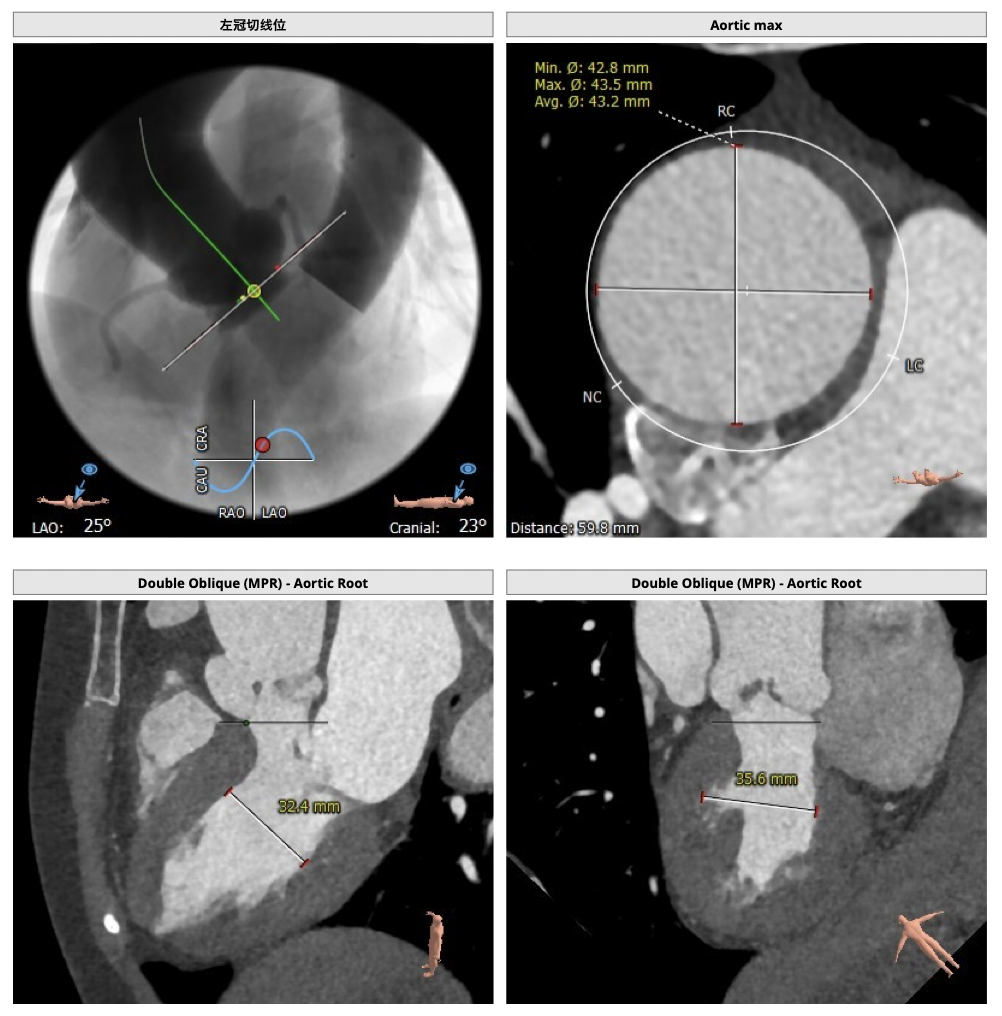

FEops评估报告

FEops评估瓣周漏

根据FEops量化评估,选用L26瓣膜高位释放会导致8.2ml/s的瓣周漏,而选用L26标准位释放会导致7.4ml/s的瓣周漏,两种释放位置产生的瓣周漏均低于发生中度至重度瓣周漏临界值16ml/s,所以两种释放位置均可以纳入考虑范围,由FEops模拟瓣周漏的3D建模得知发生瓣周漏的主要区域为左右交界处的钙化位置。

L26号瓣膜标准位释放

L26号瓣膜高位释放

FEops评估瓣膜稳定情况

根据FEops评估的L26瓣膜标准位释放结果,发现瓣膜起始位置与稳定位置有较大的改变,判断发生下滑可能性比较大,建议使用VenusA-Plus®可回收输送系统保障手术安全。

瓣膜植入前

瓣膜植入后